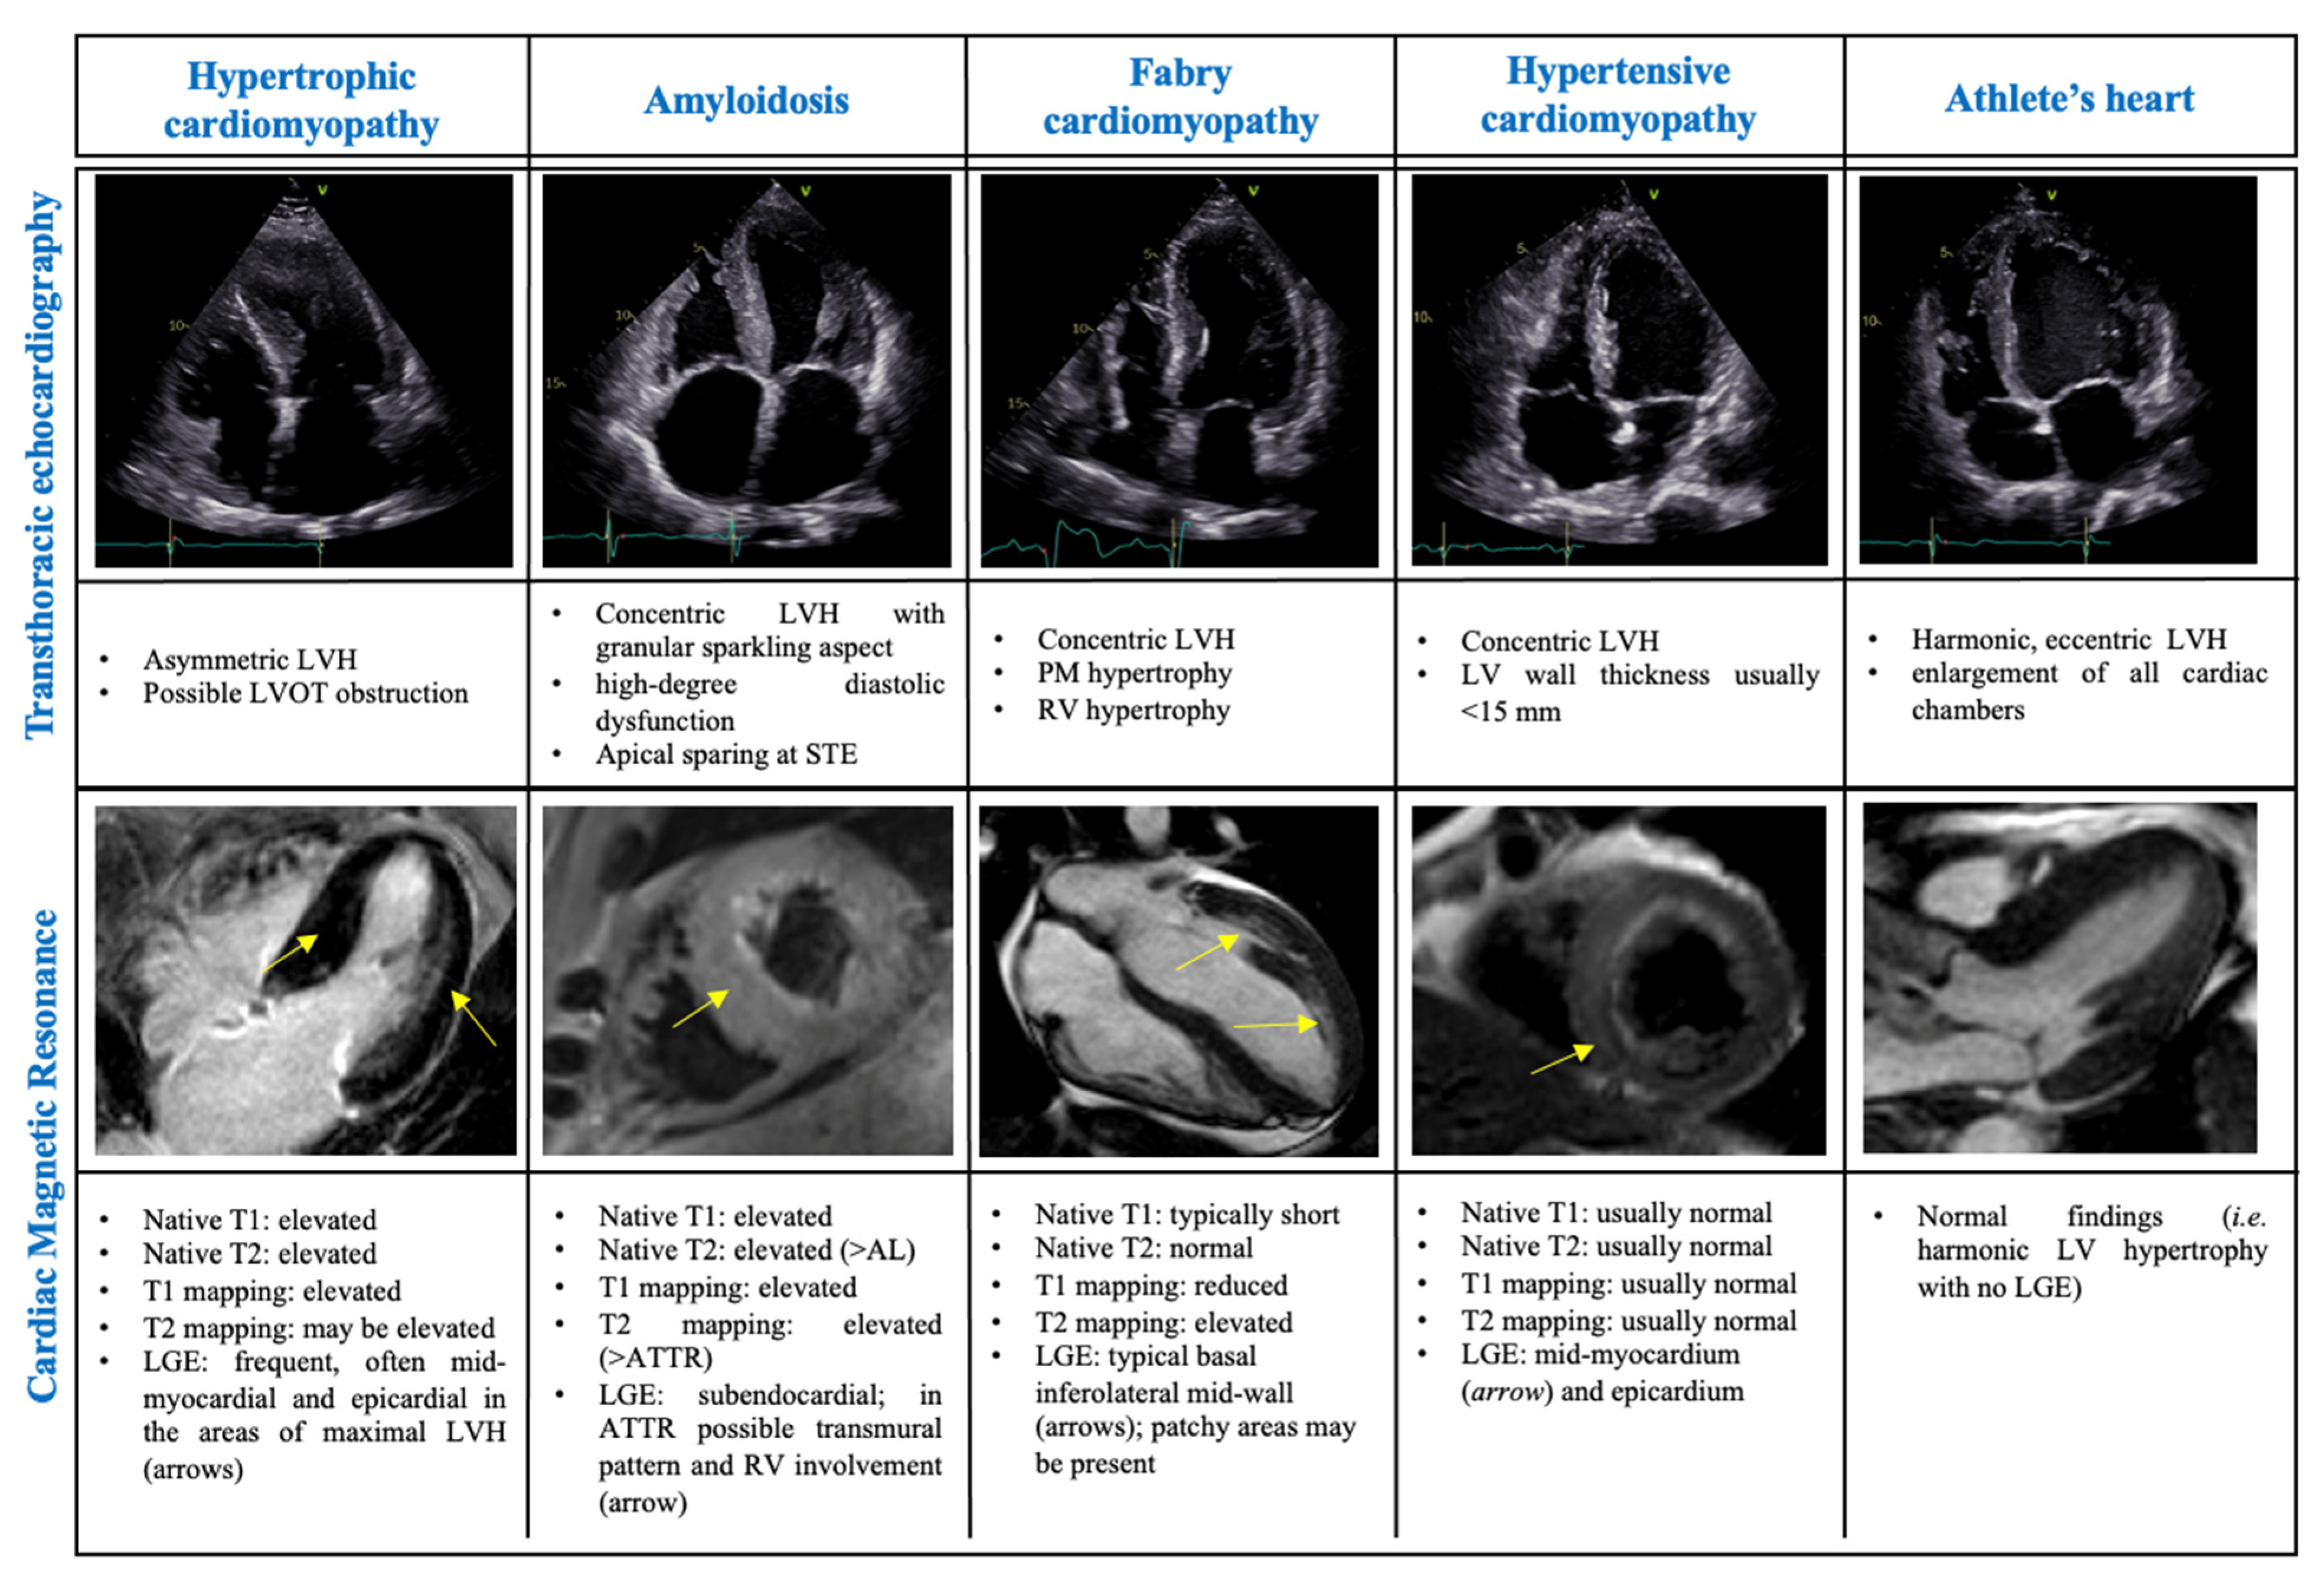

3.1. Differential Diagnosis of Phenocopies

3.1.1. The Athlete’s Heart

3.1.2. Amyloidosis

3.1.3. Hypertensive Cardiomyopathy

3.1.4. Fabry Cardiomyopathy